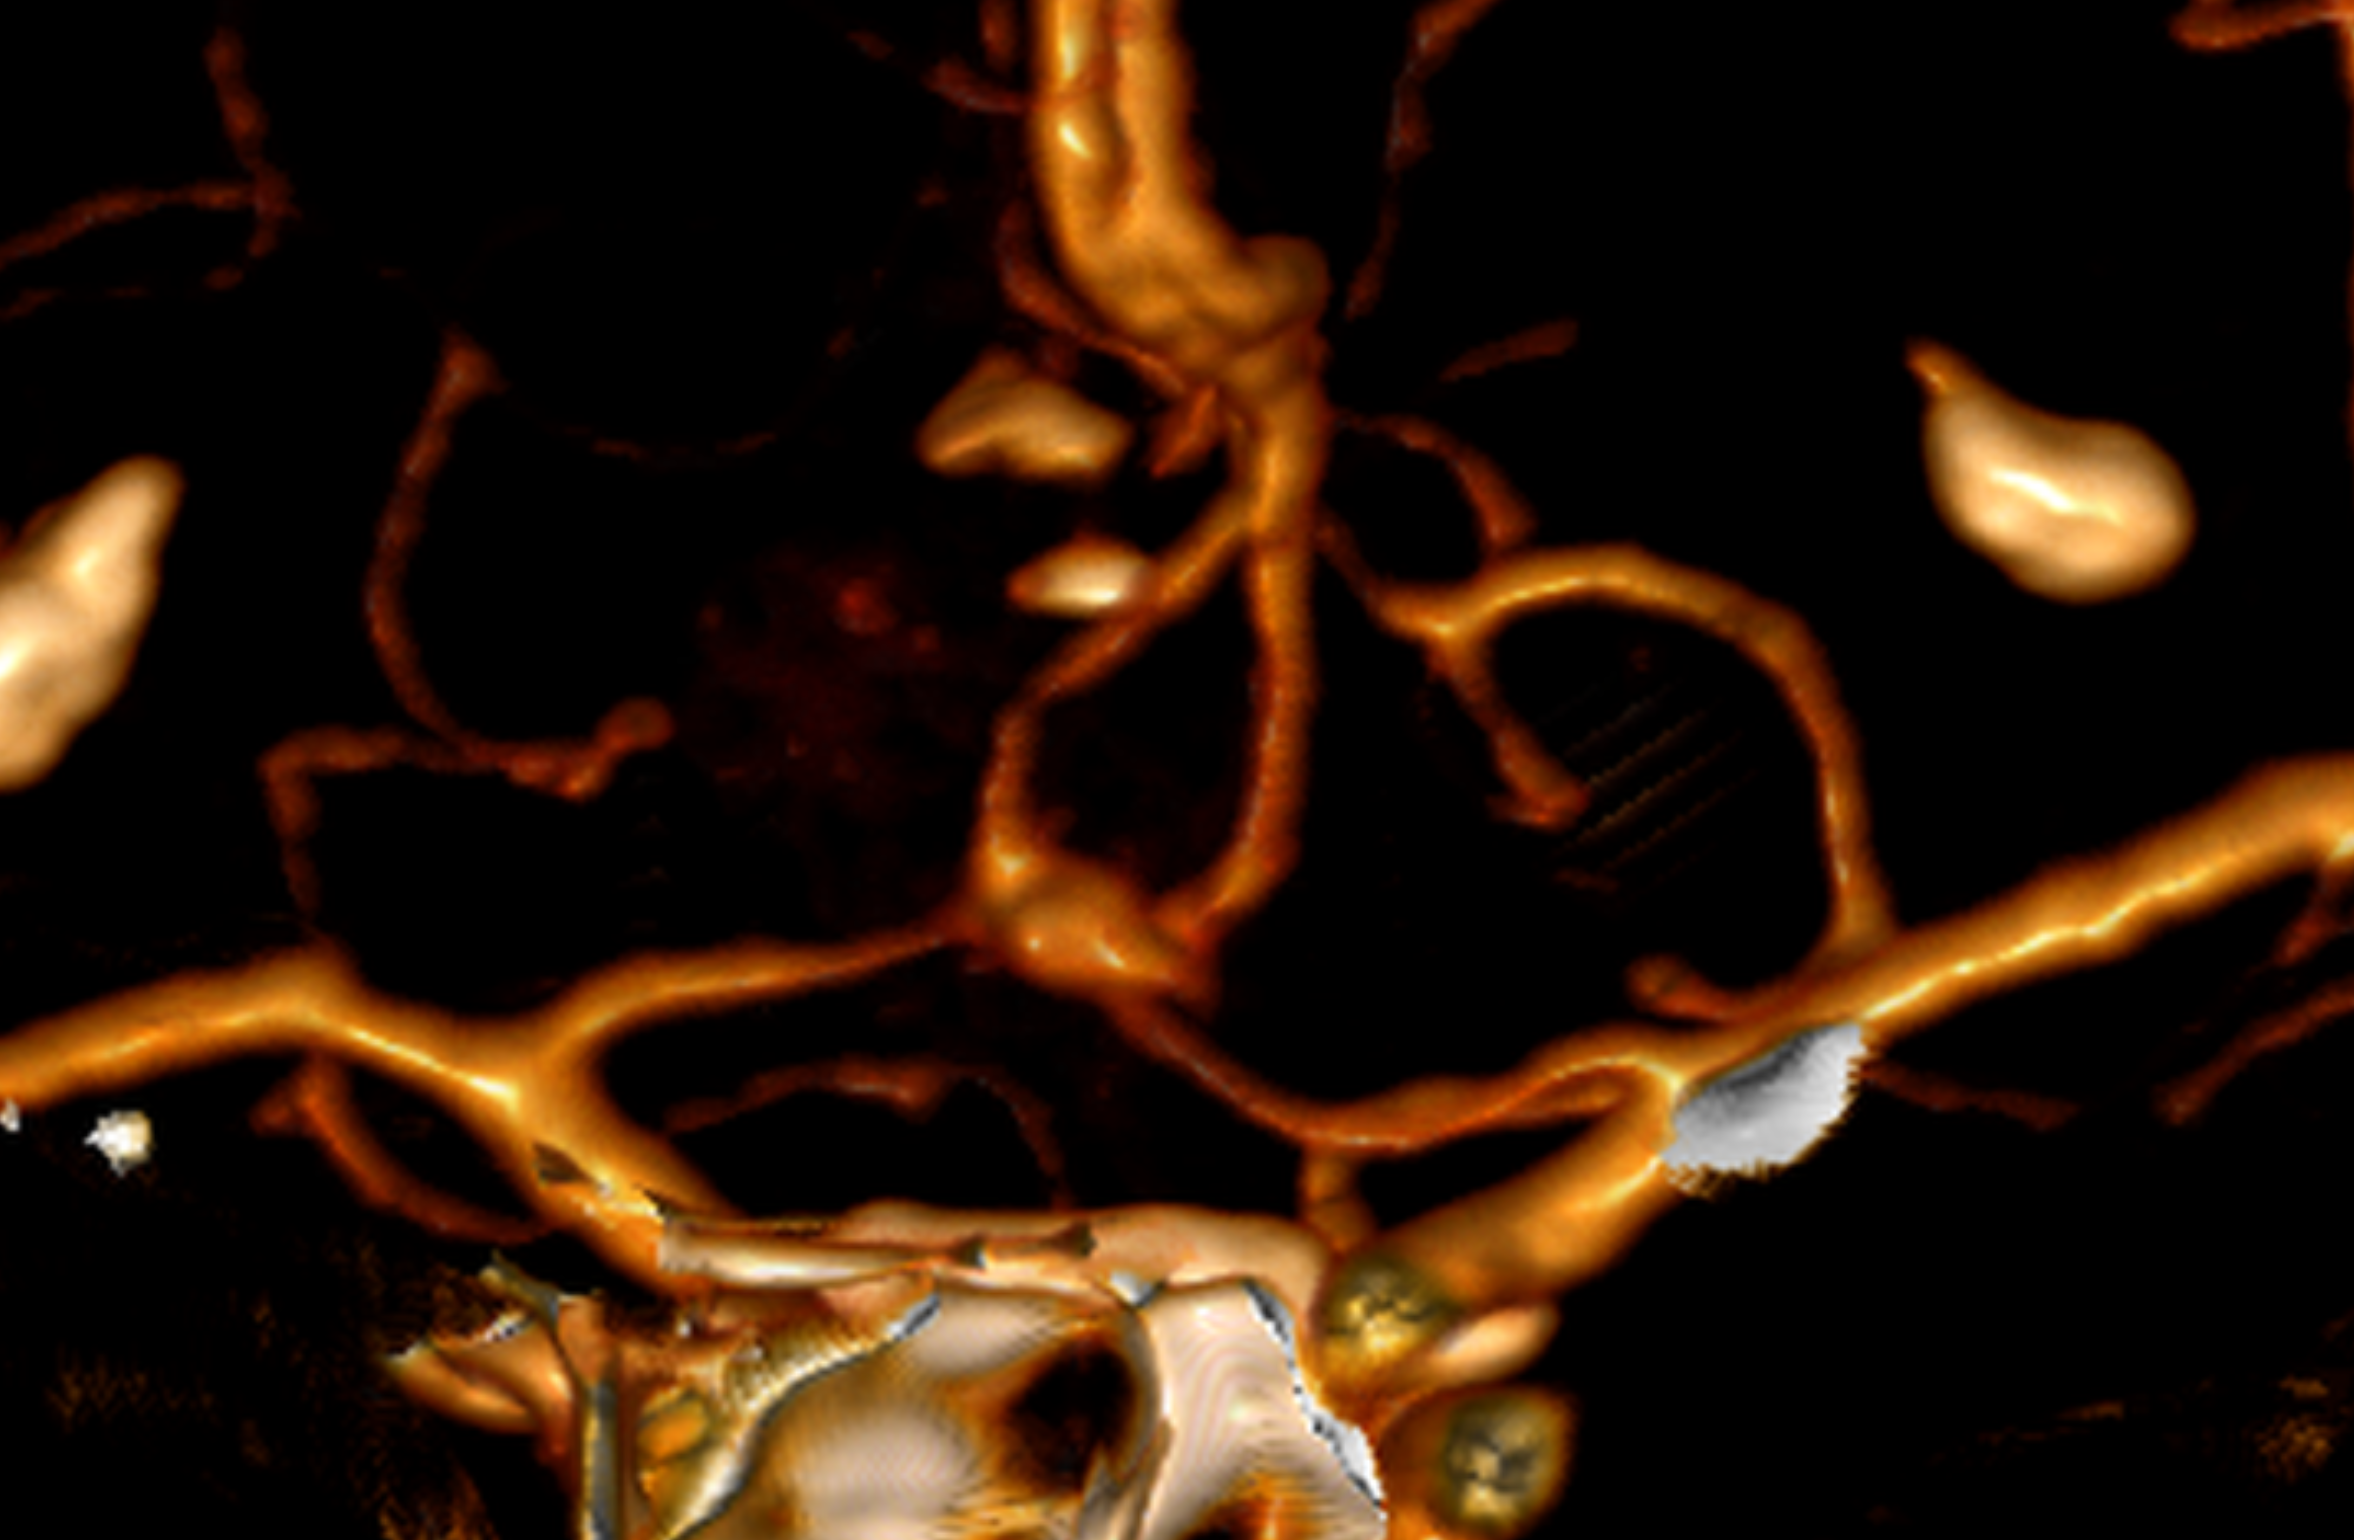

Recurrent aneurysm seen near clips

3D brain angiography showing an aneurysm